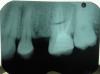

Book Опубликовано 6 июня, 2011 Поделиться Опубликовано 6 июня, 2011 Добрый день. Помогите, пожалуйста. Сильные боли в правой верхней челюсти. Врачи говорят, что все в порядке. На снимках ничего им не видно. Я думаю, что болит 16, но точно сказать не могу. Боли усиливаются к ночи, днем ноет, но терпимо. 16 вскрывали, прочистили каналы, поставили пломбу, боли не прошли. Меня направили к эндодонтисту, чтобы еще раз прочистил все каналы, это стоит дорого и я не знаю, поможет ли это лечение. Мой стоматолог сказал, если эндодонтист не поможет, тогда на резекцию верхушки корня. Скажите, пожалуйста, что вы видите на снимке. Могут ли быть боли от 7-ки? Стоит ли идти к эндодонтисту или лучше удалить зуб и поставить имплантат. Не знаю уже к кому обратиться. Спасибо.P.S. Прилагаю снимки, не знаю, на каком лучше видно. Ссылка на комментарий

Book Опубликовано 6 июня, 2011 Автор Поделиться Опубликовано 6 июня, 2011 Похоже на невралгию II ветви тройничного нерва...Конечно терапевты могут сказать еще о 4 канале в 6 зубе... В общем нужна полноценная диагностика чтобы избавиться от проблемы. Т.е проблема может быть не в зубах... Вы из какого города? Скажите, пожалуйста, а 4 канал судя по снимку не найден и не прочищен? правильно я понимаю, потому что стоматолог, который чистил каналы, сказал, что все нашел, а эндодонтист говорит, что 4 ый не найден, я не знаю, стоит ли соглашаться на поиски четвертого, вдруг не поможет. Я живу в Германии Ссылка на комментарий

Aldo Rain Опубликовано 6 июня, 2011 Поделиться Опубликовано 6 июня, 2011 4 канала может и не быть, на дентальной компьютерной томографии его можно было бы лицезреть я думаю. А что было с 5 зубом, почему удалили? И почему депульпировали 6? Какие были жалобы, опишите подробнее немного Ссылка на комментарий